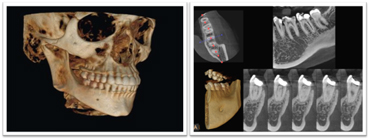

CTは立体的な画像で写し出されるため、インプラントのための診査や歯周病の程度、根管治療、親知らずの状態の把握を正確に行うことができ、より安全、確実に治療することができます。

歯科用CT(ヨシダトロフィーパンプラス)にてアゴの骨の立体的な形態や、神経の位置把握、さらに骨密度の診査などを調べます。

CTでより精密なインプラント治療が可能になります

CTによる3次元画像により、通常のレントゲン写真ではわからなかった部分が、精密・立体的に見ることができ、インプラント治療の精度も飛躍的に向上します。

歯科治療の従来の診断を大きく変えるCTスキャンの導入により今まで2次元のレベルでの診断が3次元立体画像でのレベルに変わり多くの情報を提供してくれます。

インプラント手術や歯周病治療、歯列矯正治療、歯の根の病気に関係する治療の正確な診断・治療計画には、3次元CTによる撮影が欠かせません。